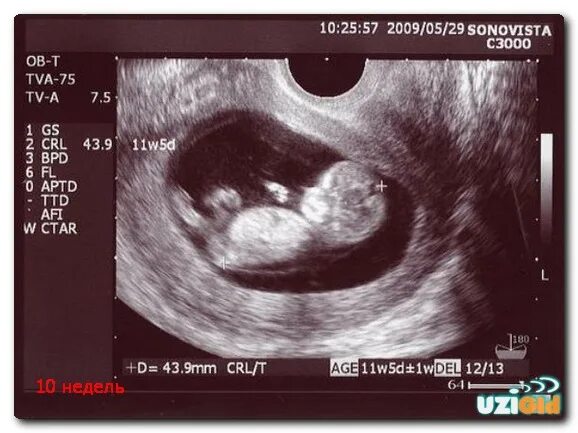

11 недель ощущения